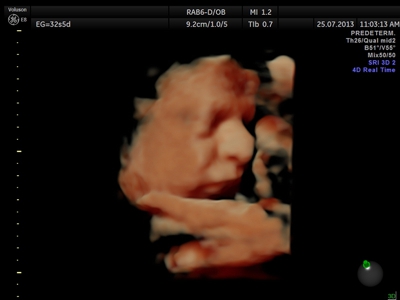

Fotografías de ecografías 4D HD/5D

Haga click sobre las imágenes para ampliar